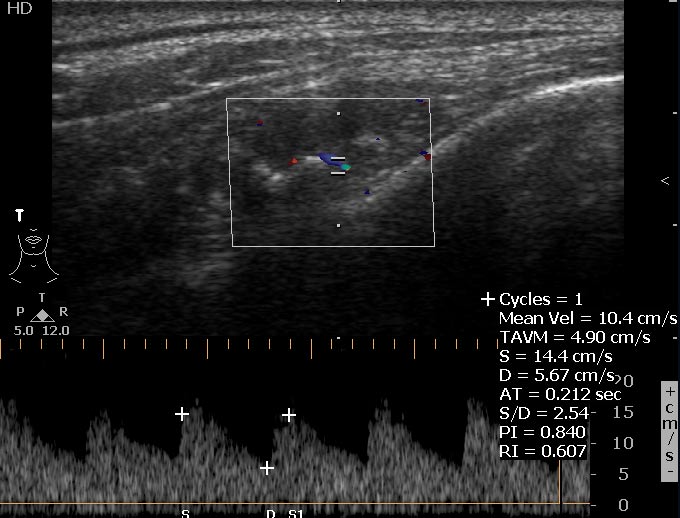

Сонограммы

Впервые встречаю подобное. Ваше мнение?

На снимке утолщение веретенообразное мышечного слоя с наличием кальцификатов(два) Кальцификаты в мышце чаще встречаются при паразитарных инфекциях(трихиниллез,токсоплазмоз,цистецеркоз),но их больше по количеству и в разных местах.Оссифицирующий миозит-имеет свою картину и распространение.Насчет Хортона-навряд ли,это же поражение сосуда.Насчет тофусов-они содержат ураты,чаще локализуются подкожно(не в мышце),при подагре осификации вдоль сухожилий.А может был удар,гематома с частичной кальцификацией?

Если в анамнезе подагра, то тогда я за скопление солей уратов. Эта гадость может накапливаться где угодно, я сам видел и смотрел публикации коллег, когда это тофусы и в брюшной полости находили, а уж в мягких тканях, так это и подавно. Тем более что это болит, кальцинированная гематома не болела бы.